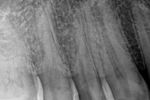

Revisionsbehandlung eines Unterkiefermolaren (37) vor geplanter Überkronung (Dr. Maik Göbbels) Download